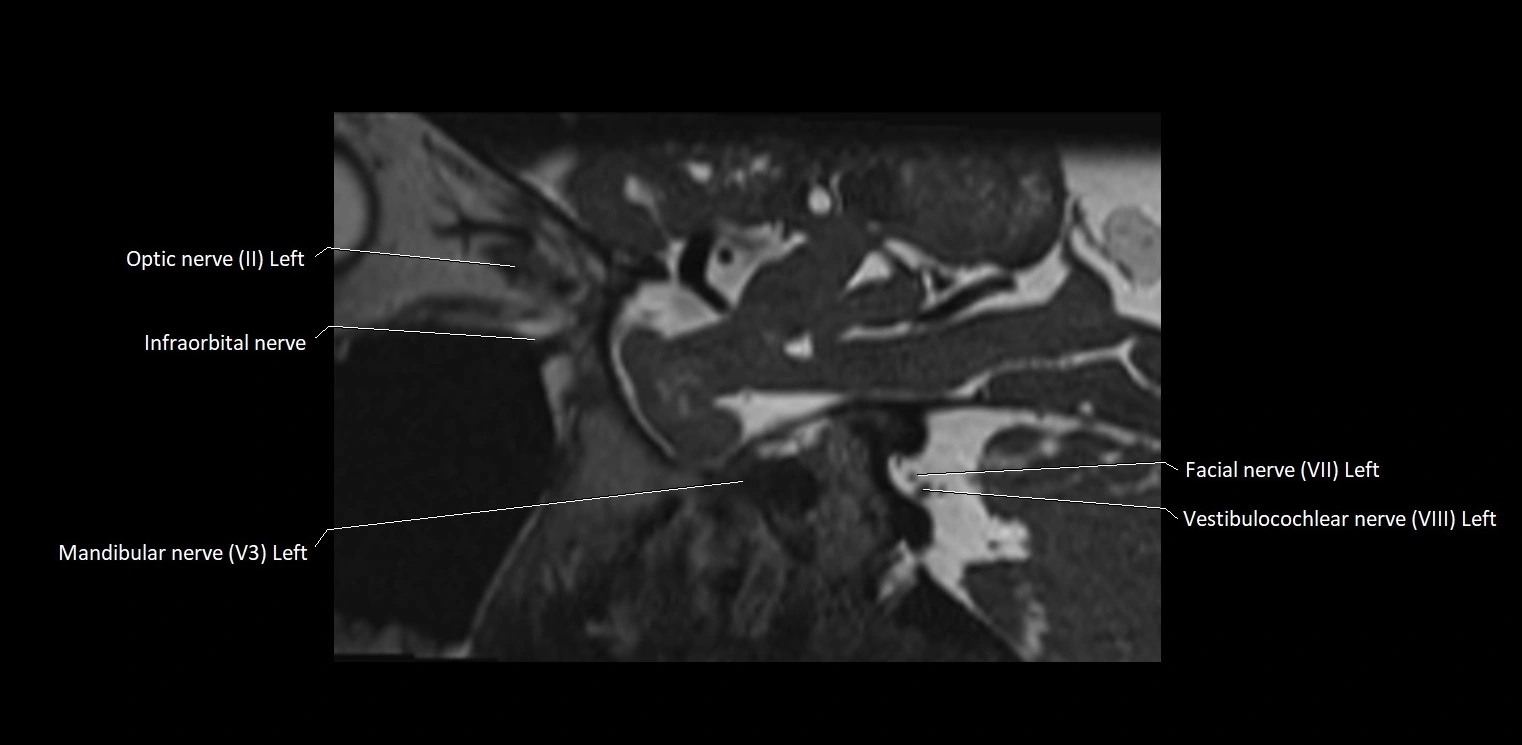

MRI images

image